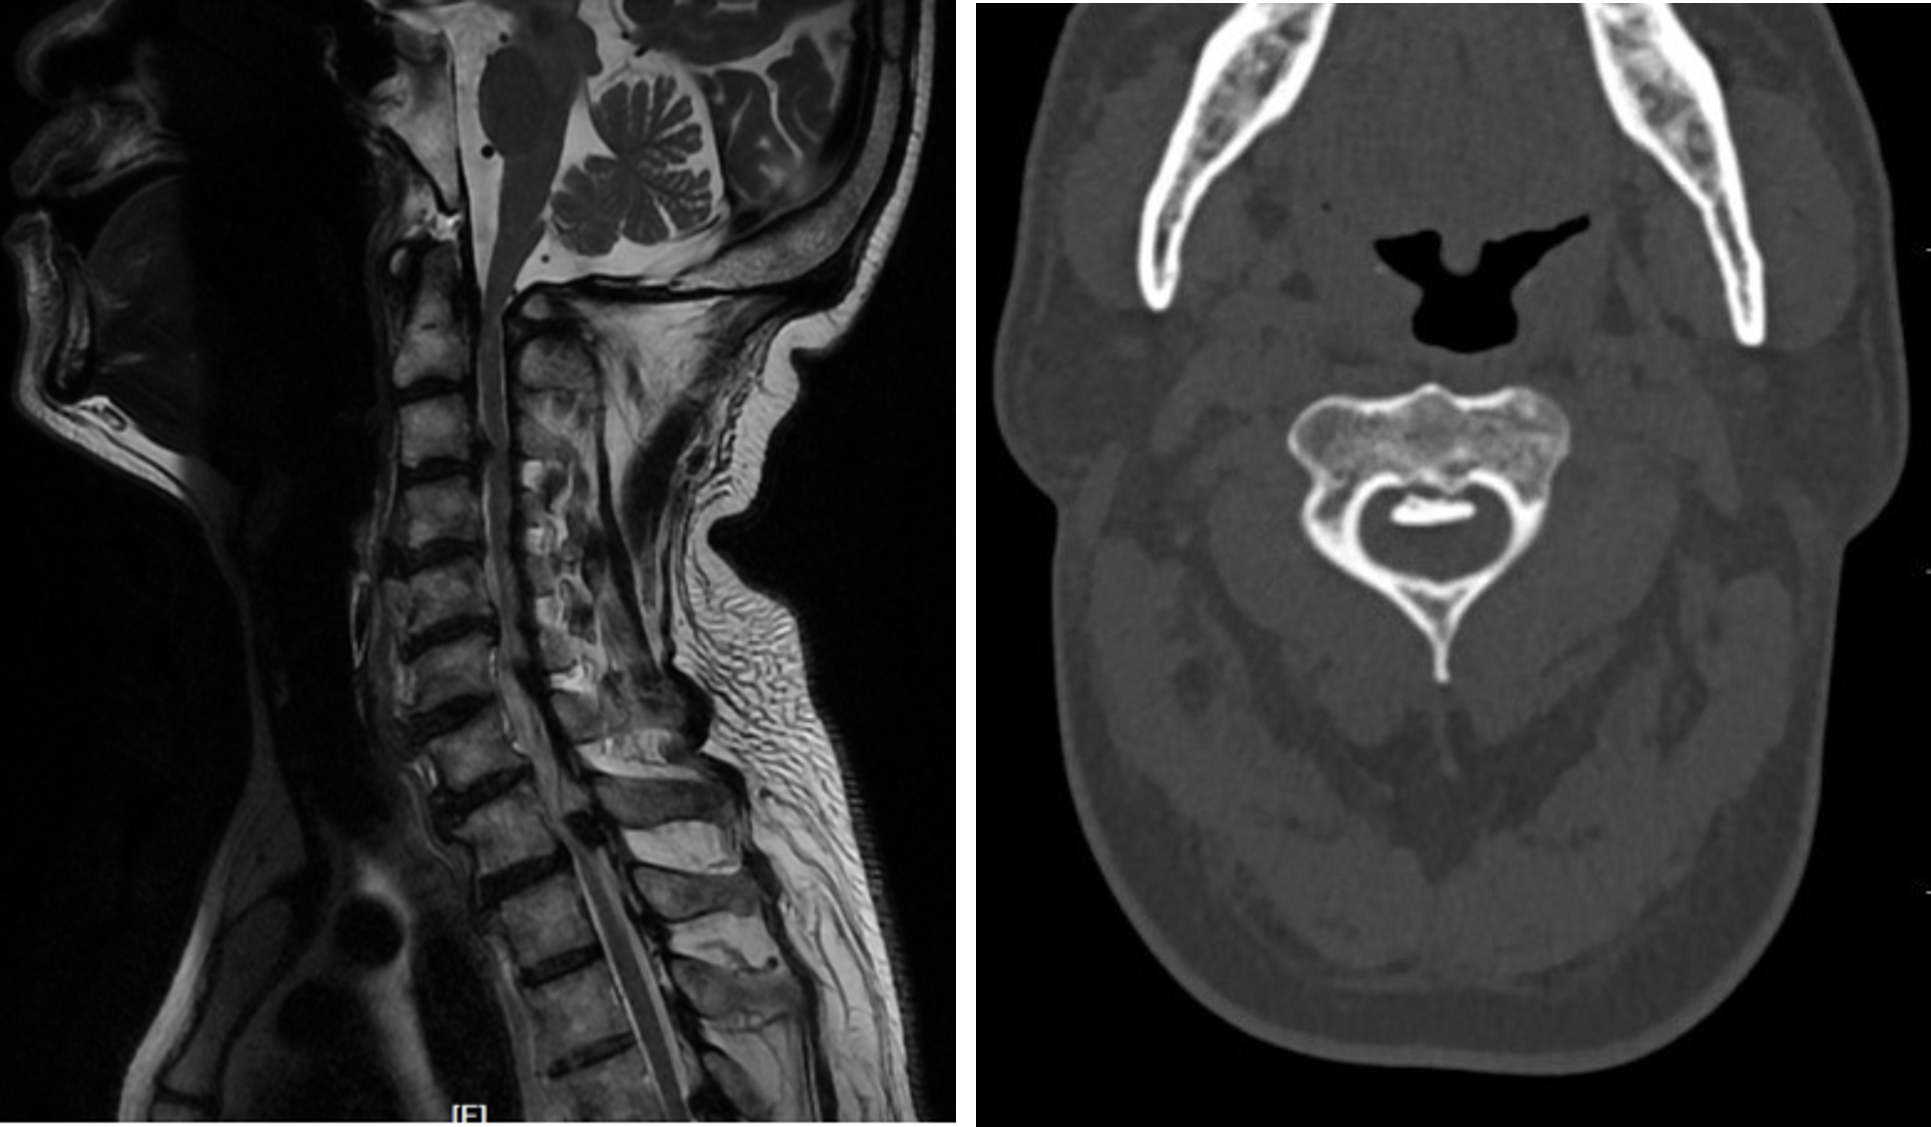

家住镇江的王先生近年来感觉自己的身体出了点问题,一开始是左脚小脚趾有点麻木,后来情况加剧,左手左脚都出现麻木的感觉,走起路来感觉像踩着棉花,这严重影响了他的生活。到当地医院一查颈椎磁共振,提示颈髓严重受压,在他的CT上看到压迫神经的主要是异常增生的骨赘(后纵韧带骨化)压迫了第1~6(下称C1~6)颈髓(第1~2颈椎由于解剖结构特别复杂,在医学上称为上颈椎)。上颈椎压迫脊髓可引起四肢麻木无力、呼吸循环功能障碍等,严重者甚至危及生命。王先生这种情况非常危险,颈髓已严重受压,就好像脖子上背了一个小炸弹,一旦他不小心摔跤,就很有可能危及生命。

王先生本就担心颈椎手术的风险,现在还涉及到上颈椎,风险更大,而不手术自己的颈椎病又将像定时炸弹一样,一直处于危险之中。就在王先生全家一筹莫展之际,听闻苏州有一位姜医生医术精湛,已帮助了许多患者解决了颈椎疾病,于是他们从家乡驱车百里,前往骨科姜为民主任的门诊就诊。姜为民主任在仔细研读过影像资料后,结合王先生的症状体征,当即决定出手为他解决病痛。入院经详细检查后发现王先生同时还患有胸椎管狭窄的问题,但当务之急是治疗高位长节段颈椎后纵韧带骨化症。